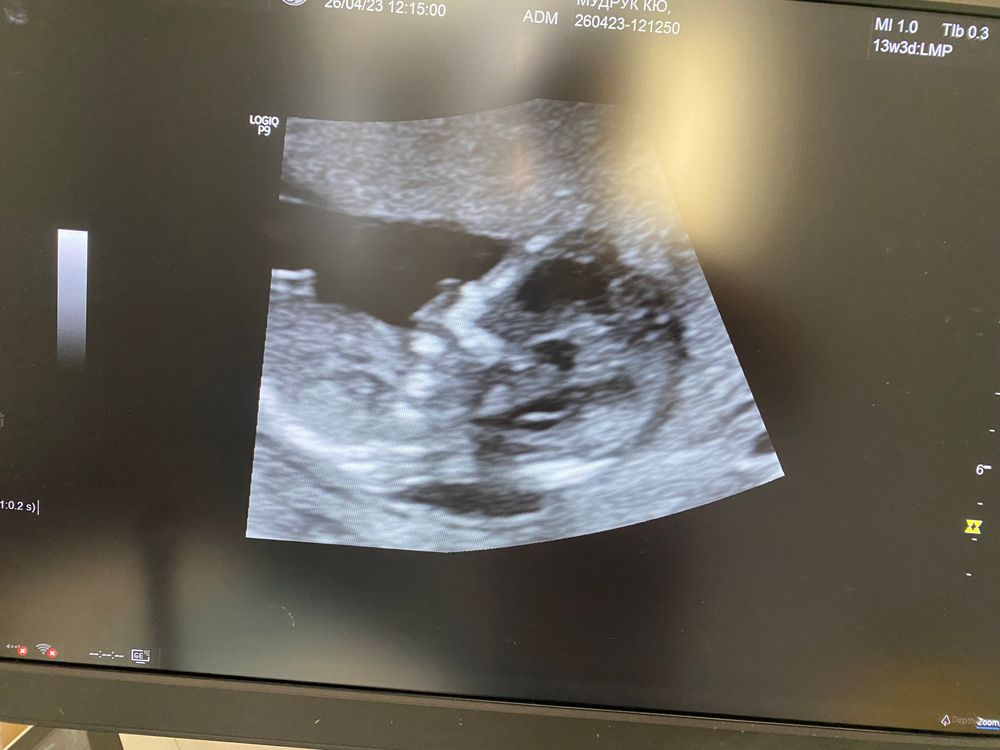

Узи 10 недель))

Кажется у вас мужичок 👍☺️

Grinch, мне тоже так показалось🤣 хотя говорят на таком сроке не видно гендер! Может зависит от размера !🤣🤣🤣

Мне сразу тоже показалось, что мальчишка. Но потом вспомнила, что в 10 недель ещё нельзя (вроде) определить пол. Возможно это пуповинка)) скорее всего, даже если и мальчишка, то большой писюнчик для такого срока)

Какой симпатичный пирожочек, и мне тоже кажется, что это сынок))) Богатое приданое на фото)))

А у вас либо мне очень кажется, либо очень хорошо видно пол ребеночка😅